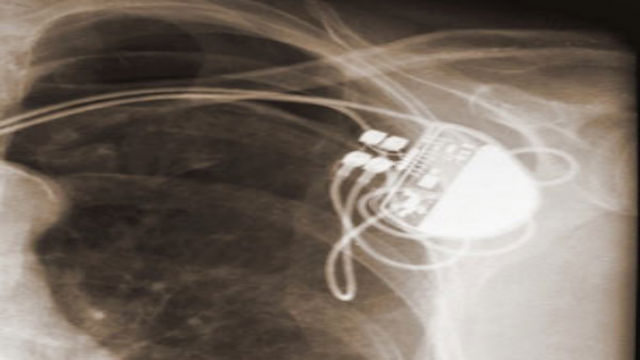

In the age of Moore’s Law and computer miniaturization, it should come as no surprise that these devices have shrunk significantly.  Now, for example, a heart’s pacemaker may be placed wholly in a self-contained apparatus resting entirely within the human chest.  There is no need for the constant connection to external devices, nor for the team of physicians to monitor the device at a patient’s bedside.  Now it is possible for a heart pacemaker to work on its own, based upon a set of pre-established operating instructions.

In the United States alone, hundreds of thousands of internal heart defibrillators have been implanted to regulate the damaged hearts of patients needing such assistance, including many well-know individuals, such as former US Vice President Dick Cheney. As a particularly polarizing public figure, it would not be surprising to learn that Mr. Cheney had a number of enemies and it was the job of the U.S. Secret Service to protect him from any threat–including any potential attacks against the critical technology implanted in his chest and upon which his life depended.